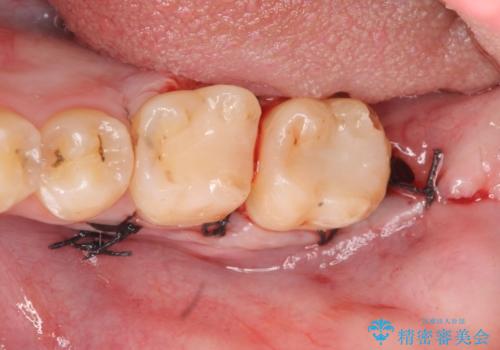

左下7の虫歯は深く、また歯冠高径も低かったため、歯冠長延長術を行いました。

術後歯肉の回復を待ち、左下6はセラミックインレー、左下7はオールセラミッククラウンにて補綴しました。

歯冠長延長術とは歯肉弁根尖側移動術とも言い、歯の高さが低くクラウン(被せ物)による治療が難しい場合に、歯茎を歯根方向に下げることで歯の高さを確保する手術です。歯の高さが十分にあることで、外れにくいしっかりとしたクラウンを被せることができます。